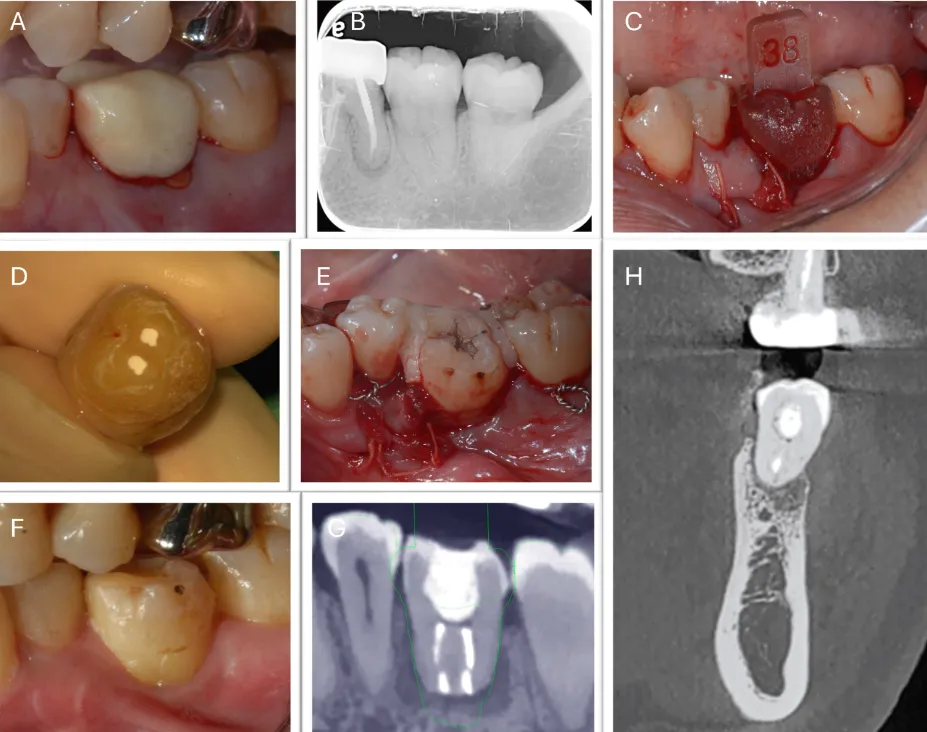

2025年的一篇病例报告,首次报道了动态导航系统在自体牙移植术中的应用(图10、11)。该系统通过实时监控牙槽窝预备过程的深度与方向,显著提高了牙槽窝制备的精确性,增强了手术的可控性与可预测性,同时最大限度地降低了对邻近组织的损伤风险。

图10(图引自Chen X, Li J, Zhang Y, Wang H. Navigation-guided autotransplantation: a novel technique for precise and predictable tooth placement. J Oral Maxillofac Surg. 2023;81(4):345-352. doi:10.1016/j.joms.2022.12.005.)结合动态导航技术的自体牙移植:(A)术前口内照;(B)术前根尖片;(C)3D打印供体牙模型试戴;;(D)根尖切除、根管倒预备及倒充填;(E)供体牙就位并固定;(F)术后2个月口内照;(G)术后2个月CBCT矢状位截图;(H)术后2个月CBCT冠状位截图

图11(图引自Chen X, Li J, Zhang Y, Wang H. Navigation-guided autotransplantation: a novel technique for precise and predictable tooth placement. J Oral Maxillofac Surg. 2023;81(4):345-352. doi:10.1016/j.joms.2022.12.005.):动态导航技术在自体牙移植术中的应用:(A、B)36近中根、远中根及根分叉的手术导板规划;(C)设计的6个手术导板;(D)采用X-Guide®导航系统进行受牙区牙槽窝预备(冠状面、矢状面及咬合面视图);(E)黄色部分标示的是需去除的多余牙槽骨;(F)使用 X-Mark® 探针复查牙槽窝预备情况